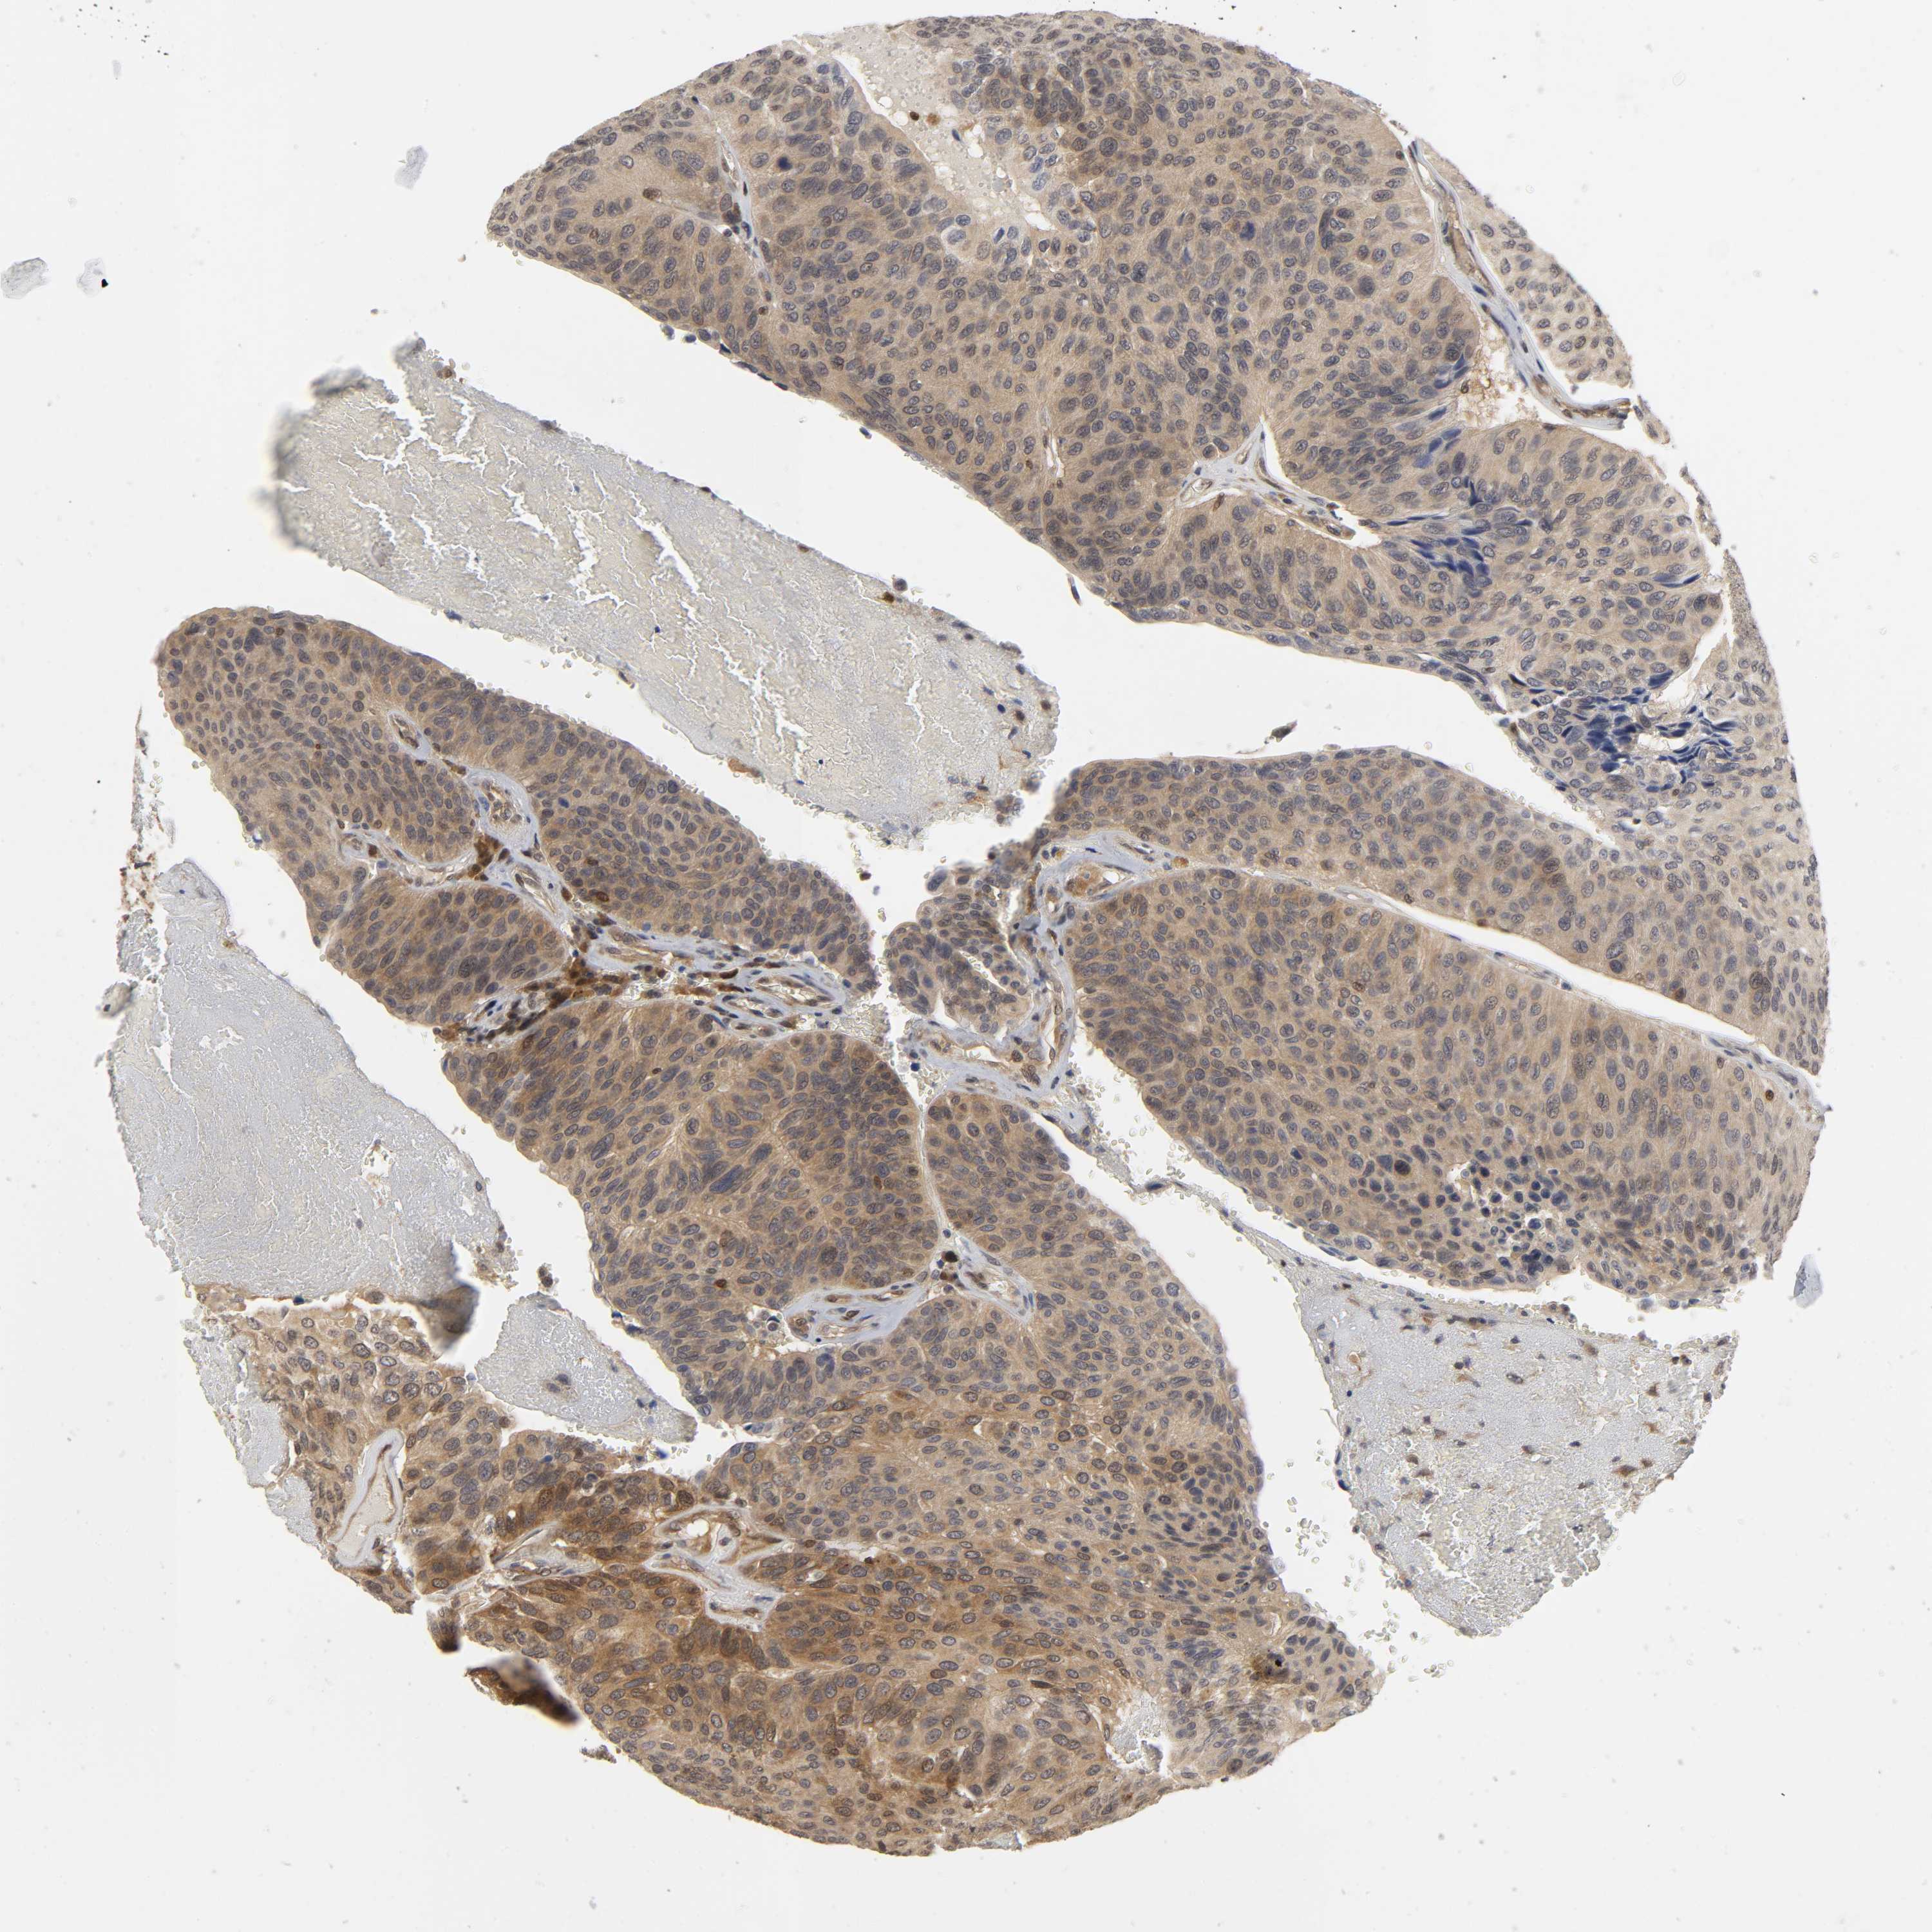

UROTHELIAL CANCER - Protein expressioni

A mouse-over function shows sample information and annotation data. Click on an image to view it in a full screen mode. Samples can be filtered based on level of antibody staining by selecting one or several of the following categories: high, medium, low and not detected. The assay and annotation is described here.

Note that samples used for immunohistochemistry by the Human Protein Atlas do not correspond to samples in the TCGA dataset.

Antibody stainingi

Antibody staining in the annotated cell types in the current human tissue is reported as not detected, low, medium, or high, based on conventional immunohistochemistry profiling in selected tissues. This score is based on the combination of the staining intensity and fraction of stained cells.

Each image is clickable and will lead to virtual microscopy that enables deeper exploration of all samples and also displays staining intensity scores, fraction scores and subcellular localization as well as patient and tissue information for each sample.

Antibody HPA004190

Antibody CAB005870

Staining

High

Medium

Low

Not detected

Intensity

Strong

Moderate

Weak

Negative

Quantity

>75%

75%-25%

<25%

None

Location

Nuclear

Cytoplasmic/membranous

Cytoplasmic/membranous,nuclear

Urothelial carcinoma, High grade

Urothelial carcinoma, Low grade